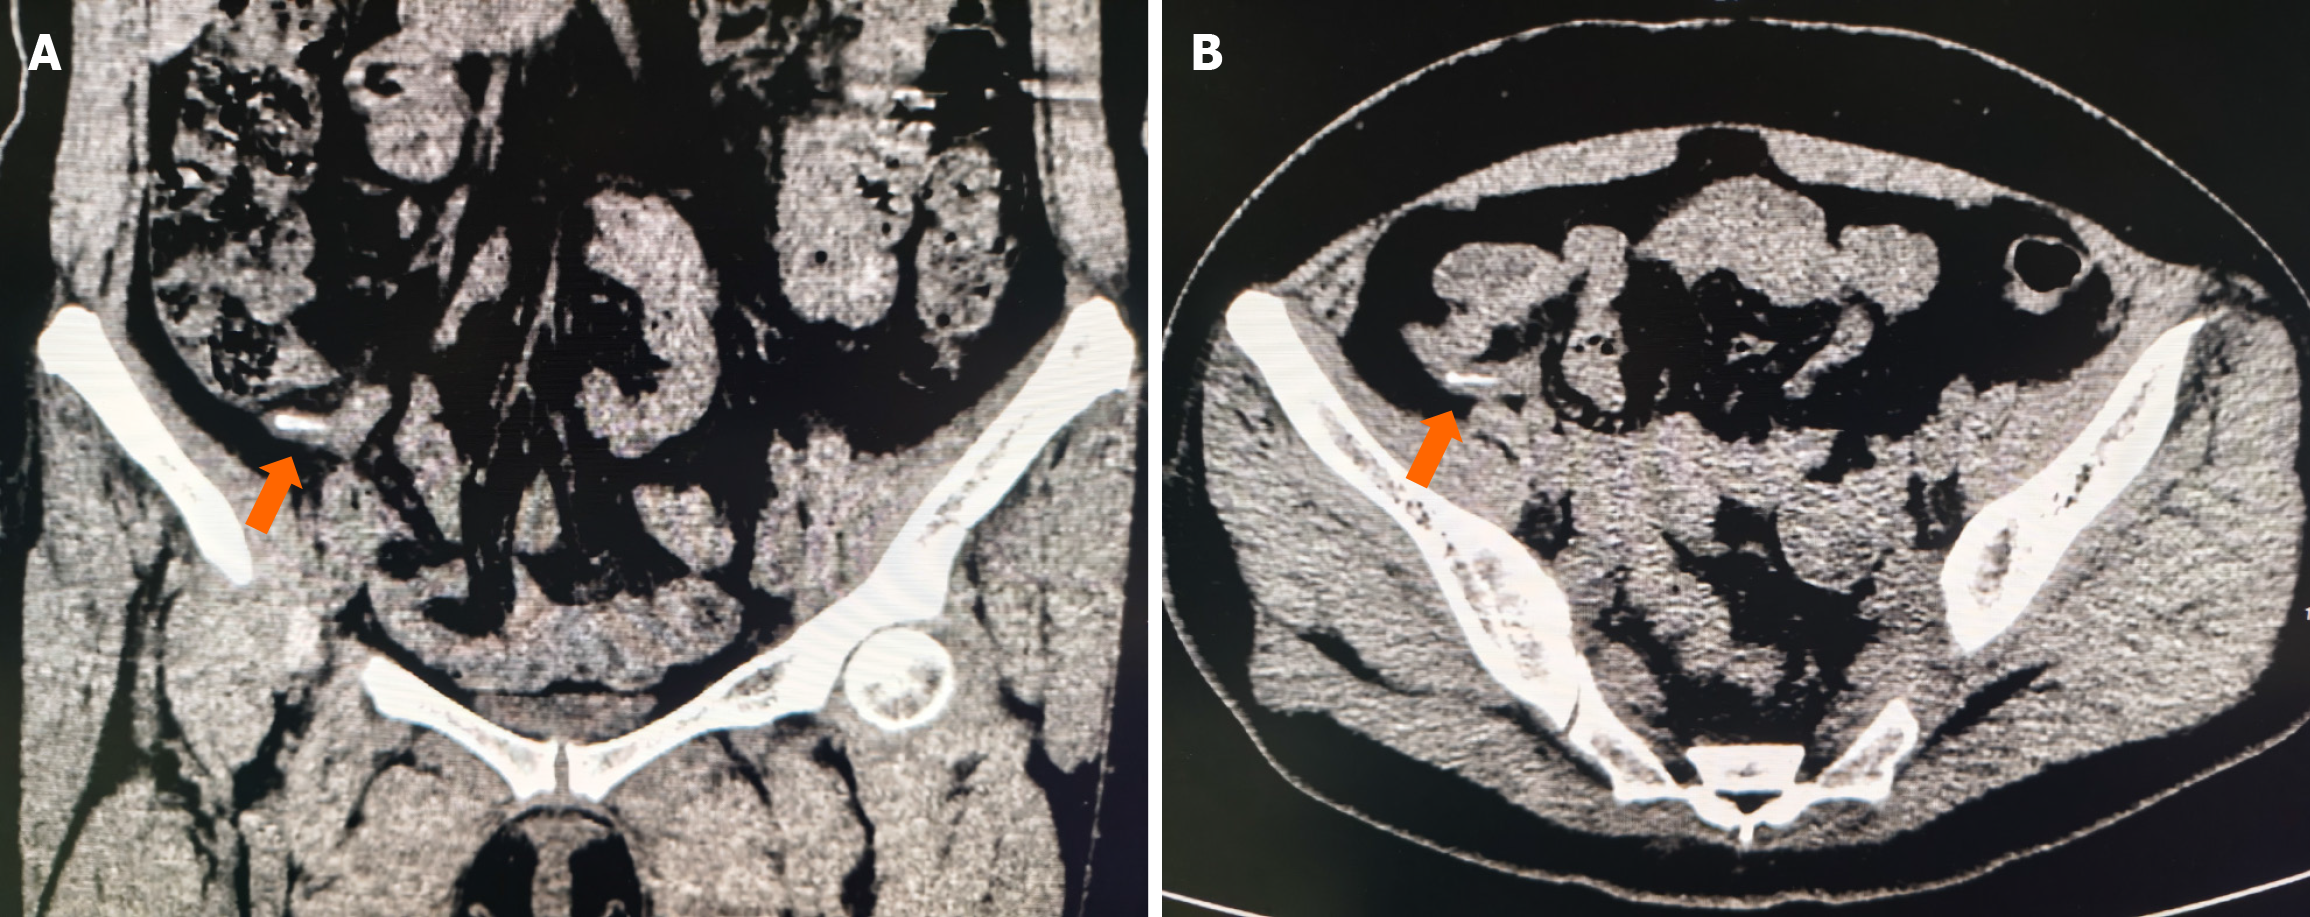

Abdominal CT scan showed high-density imaging in the appendix cavity, which raised the possibility of foreign bodies (Figure 1).

Chronic appendicitis caused by foreign bodies has not been reported to date. We report an extremely rare case of chronic appendicitis caused by foreign bodies in the appendix. The cause of the patient's long-term abdominal pain was still unclear, and she was repeatedly treated in several hospitals. Abdominal color ultrasound examination indicated that there was coprolith in the appendix, the appendix was normal structurally, and the degree of abdominal pain was mild, so surgery could not be performed. After empirical antibiotic treatment, the patient's abdominal pain was gradually relieved, but abdominal pain often recurs. Other reasons, such as chronic enteritis, chronic pelvic inflammation, etc. which may cause chronic abdominal pain were excluded. Abdominal CT examination revealed a high-density image in the appendiceal cavity. According to radiologists, foreign bodies in the appendix were considered instead of coprolith, and laparoscopic appendectomy was performed upon the request and consent of the patient. Postoperative incision of the appendiceal specimen revealed chicken bones in the appendiceal cavity. The patient recovered and was discharged after surgery. Abdominal pain did not recur during 2 months follow-up. Therefore, it is particularly important that we carefully assess imaging findings and multidisciplinary diagnosis when facing atypical symptoms.